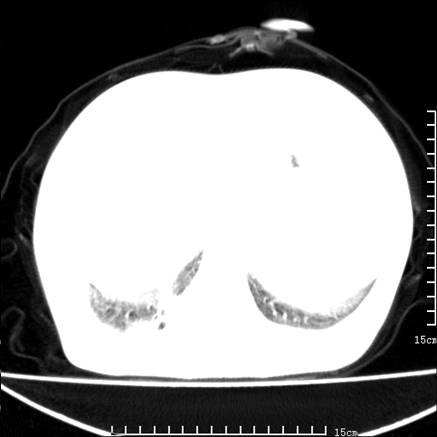

女,王某,58岁,咳嗽三个月余,基层医院二个月前诊为肺结核,用抗结核药二个月无明显疗效。

心包积液致肺瘀血.右侧周围型肺癌伴肺内转移,中间裂积液,叶间胸膜肥厚.右上肺大泡,右侧胸膜肥厚.

双肺继发型tb,心功能不全并肺淤血、心包、双侧叶间裂积液,肺大泡,右下胸膜肥厚钙化。